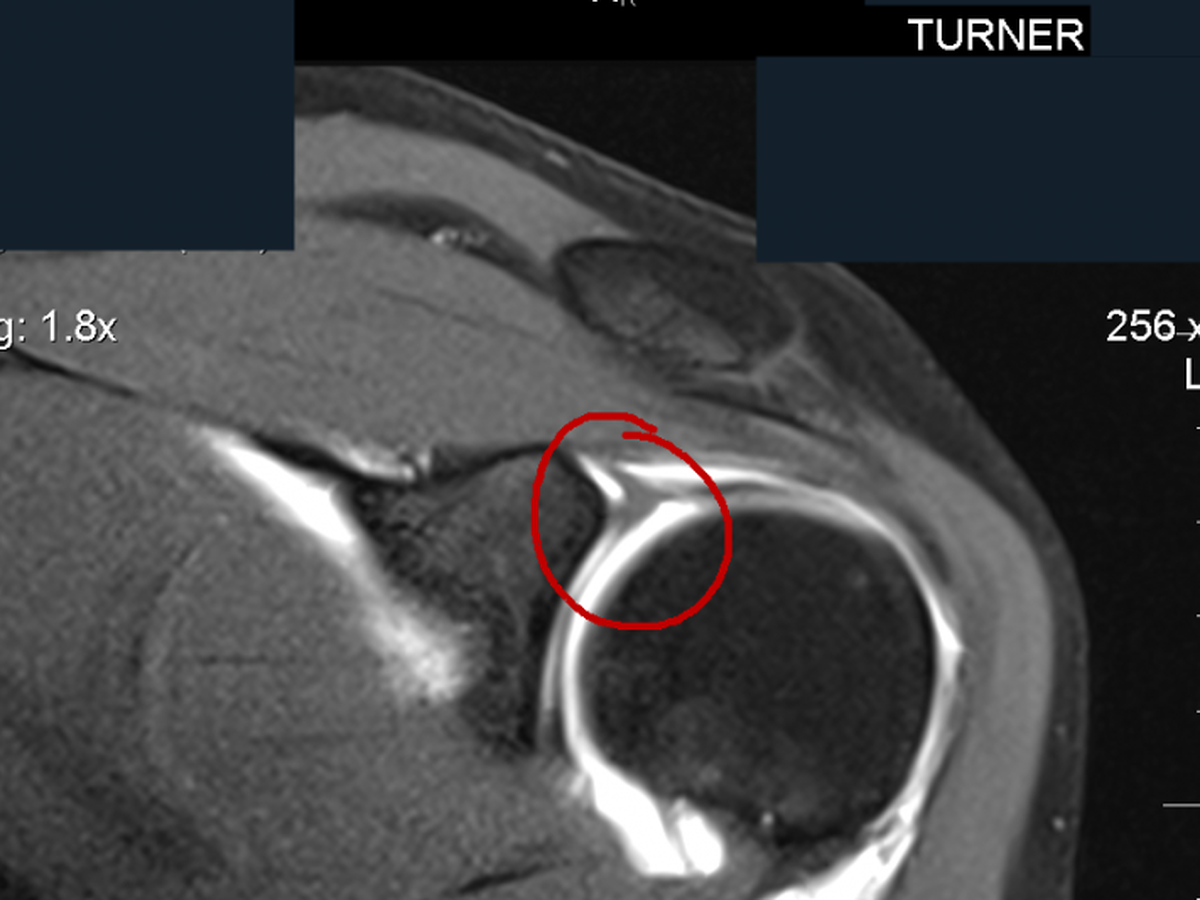

At the end of 8 weeks however, I still had constant pain and continued weakness so he sent me for an MRI Arthrogram. A 3" long 22 gauge needle was inserted into my left shoulder and 12ml of contrast was injected ahead of an MRI.

Friday, July 28th I got my diagnosis: "Left superior labral tear extending along the posterior superior quadrant"